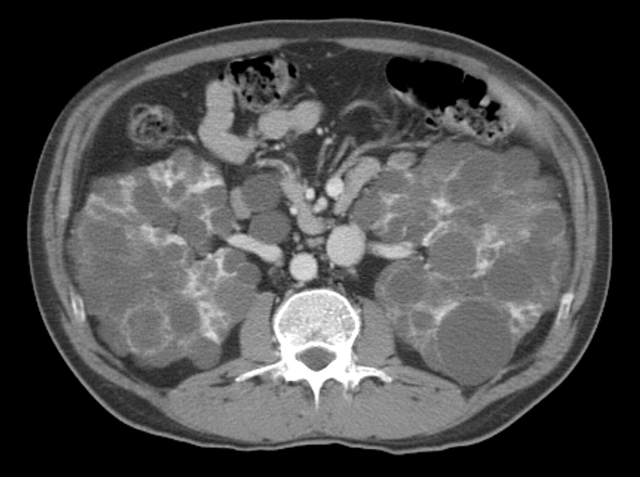

多囊肾还是双肾囊肿

图片尺寸2592x1936

多囊肾